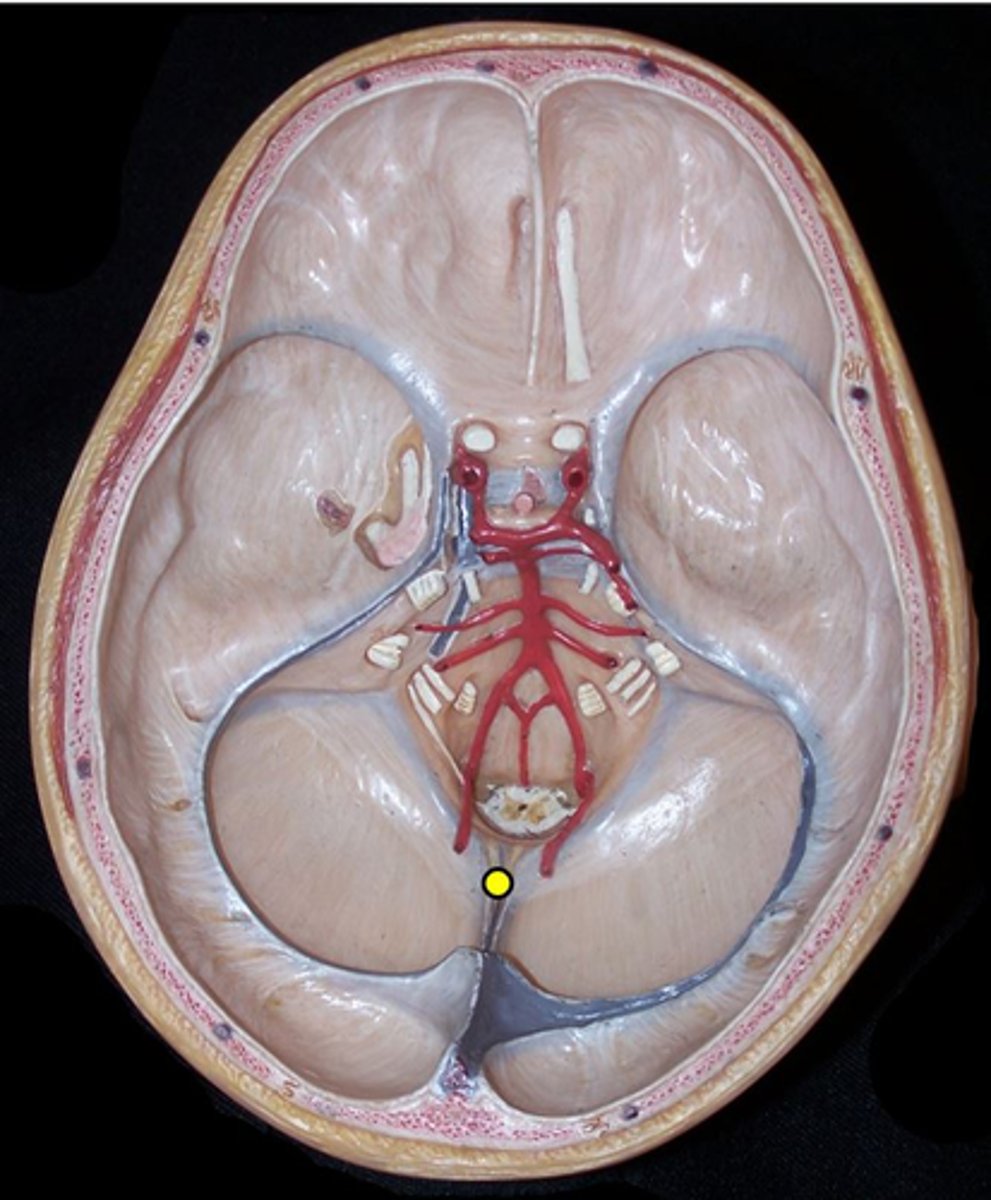

Optic chiasm

point at which optic nerve fibers cross in the brain

Optic nerve

Optic tract

Tectum

Superior colliculi

Inferior colliculi

Corpora quadrigemina

ALL four together

Olfactory nerve

CN I

olfactory tracts

olfactory bulbs

Optic nerve

CN II

Occulomotor nerve

CN III

Trochlear Nerve

CN IV

Trigeminal Nerve

CN V

Abducens Nerve

CN VI

Facial Nerve

CN VII

Vestibulochochlear Nerve

CN VIII

Glossopharyngeal Nerve

CN IX

Vagus Nerve

CN X

Accessory Nerve

CN XI

Hypoglossal nerve

CN XII